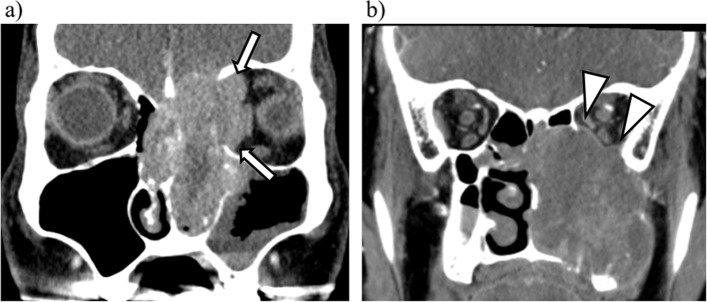

Fig. 4.

Representative cases diagnosed as false-negative and false-positive with the trained CNN model. a A patient with left ethmoid sinus cancer. As the tumor involved the extraocular muscles and obliterated orbital fat with medial orbital wall destruction (white arrow), the final diagnosis by experienced radiologists was determined as invasion-positive. However, the CNN model-based diagnosis was negative (a false negative). b A patient with left maxillary sinus cancer. As a thin membrane structure bordering the tumor and the intraorbital fat could be identified (white arrowhead), the final diagnosis by the experienced radiologists was invasion-negative. However, the CNN model-based diagnosis was positive (false positive)